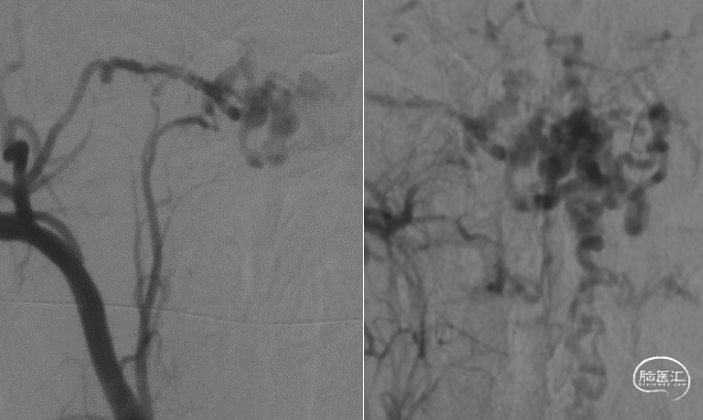

男性,34岁。主因“头痛、头晕伴头颈部麻木40天余”入院。既往病史无特殊。入院查体可见右侧病理征阳性,右侧C2-4前感觉减退。外院检查提示高位颈髓水肿,髓周血管瘤空影。

枕骨大孔区硬膜动静脉瘘;供血:耳后动脉、咽升动脉、椎动脉脊膜支。

手术过程及术后恢复顺利。术后原有症状明显缓解。术后复查造影提示瘘消失。